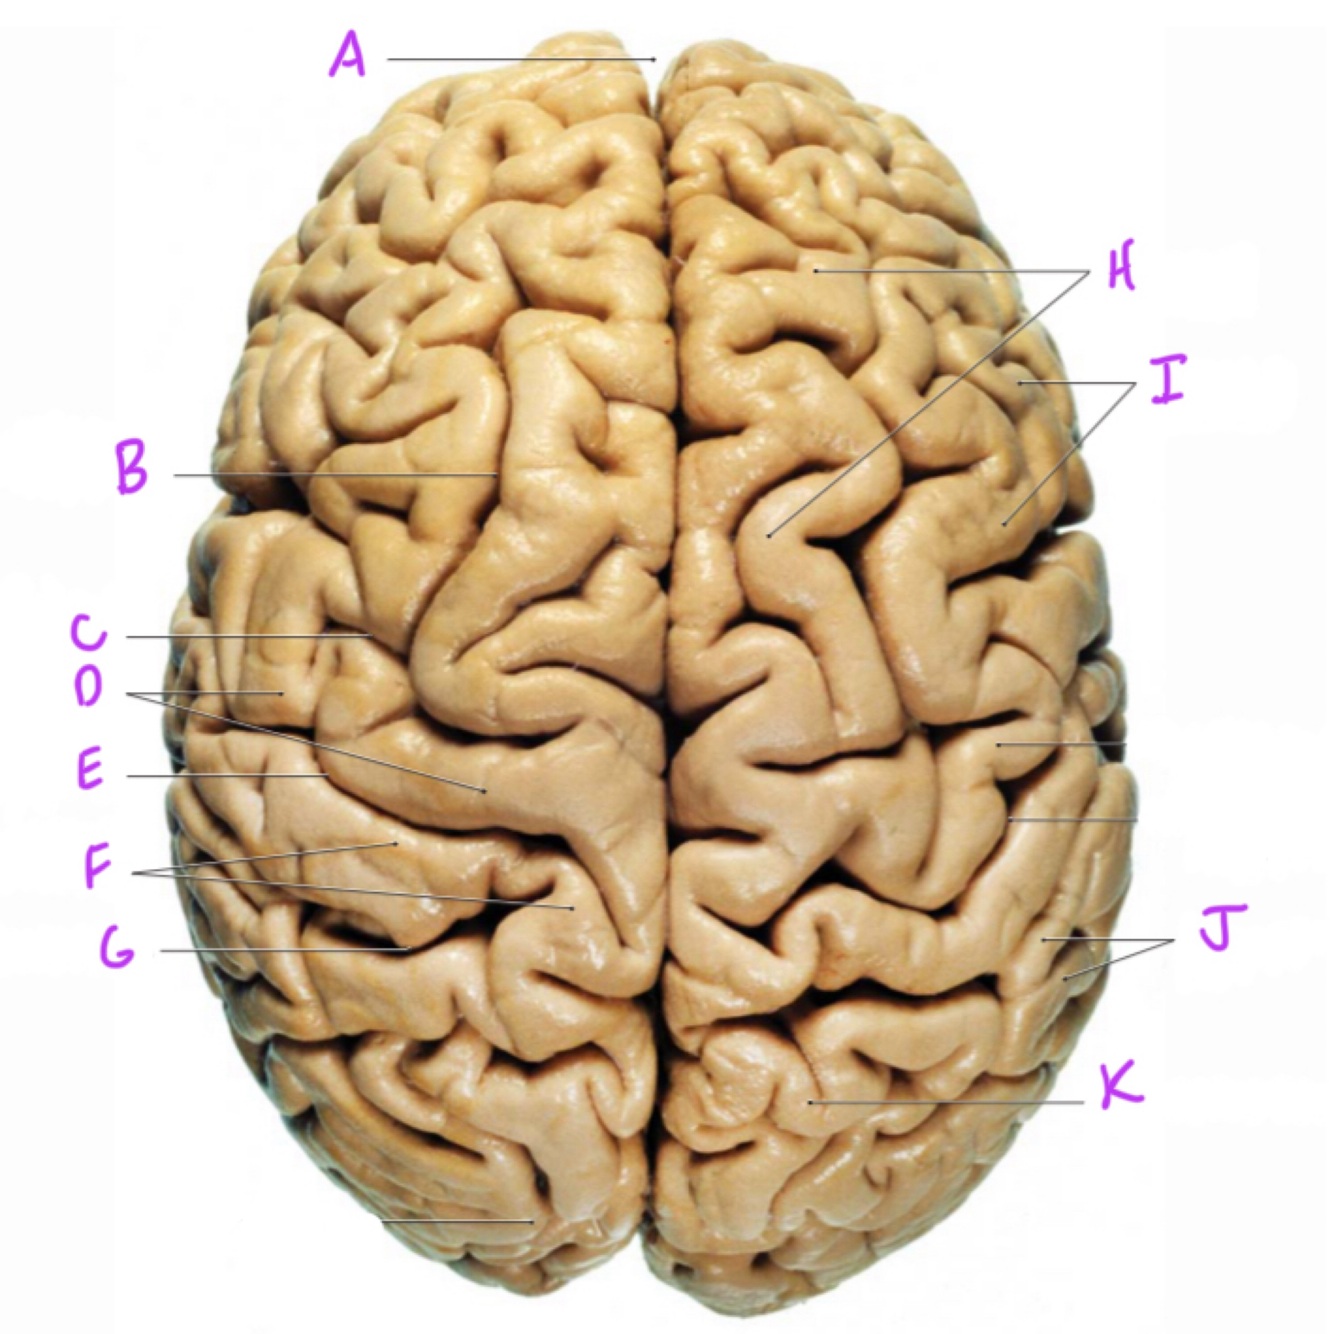

A

longitudinal fissure

Q

superior frontal sulcus

11

precentral sulcus

12

precentral gyrus

13

central sulcus

14

postcentral gyrus

15

postcentral sulcus

16

superior frontal gyrus

17

middle frontal gyrus

18

supramarginal gyrus

19

superior parietal lobule